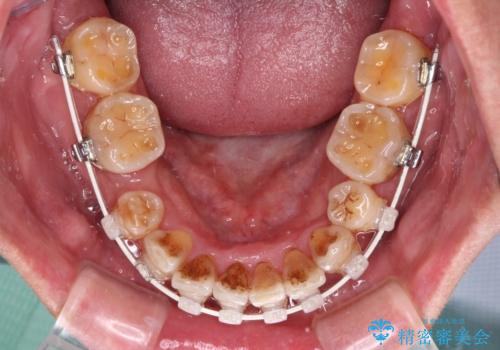

- 矯正装置

- 審美装置

- 骨格的な咬み合わせのズレ、前歯のデコボコとクロスバイトを気にして来院された患者様です。

全額的にデコボコが強いため、上下左右の小臼歯計4歯を抜歯し、ワイヤー装置による矯正治療を行うこととしました。

抜歯する歯の一部をセオリーである第一小臼歯ではなく、第二小臼歯にすることで、骨格的なずれをカバーするように計画しました。